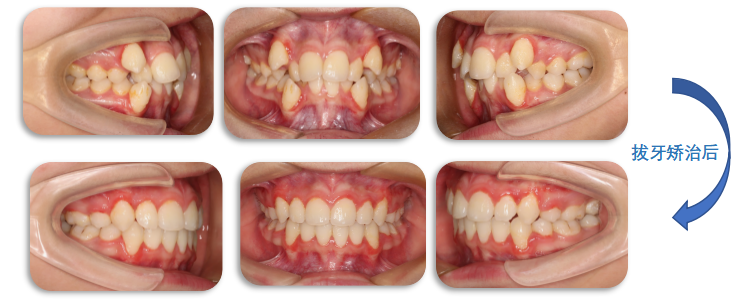

治疗前

拔牙治疗后

通过拔牙矫治,内收前牙,改善“哨牙”及突面型